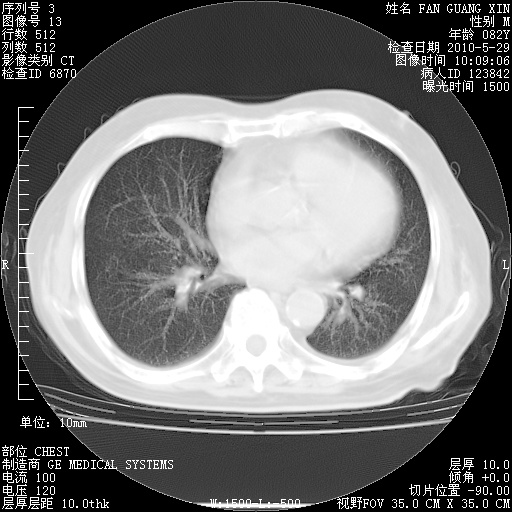

治疗3周后的肺部CT纵隔窗

从胸部影像学来看,的确有好转。至于目前为何发热不甚清楚?除了发热还有其他症状如有无喀痰,痰呈丝状吗?等等。尽量搜寻有无致发热其它可能原因?真菌?其它?如果的确无其他致发热的原因,考虑将甲强龙调至60-80mg bid/日。免疫全套基本无异常,考虑多系特发性肺间质纤维化

再治疗10天后的肺部CT

再治疗10天后的肺部CT 纵膈窗

阅读此次胸部CT,肺间质渗出性改变较入院时有吸收。目前从体温、白细胞、中性分叶明显增高,肯定存在细菌感染(发生医院感染哦,若无消化道及泌尿系统等感染的依据,肺部感染可能大)。若你院头孢哌酮舒巴坦钠耐药率较高,同意你的方案,若48小时体温仍高,可考虑使用碳青霉稀类抗菌药物,同时可予超声雾化、注意滴数时加大液体量。白蛋白33.30g/L较低哦,需加强营养等支持治疗。